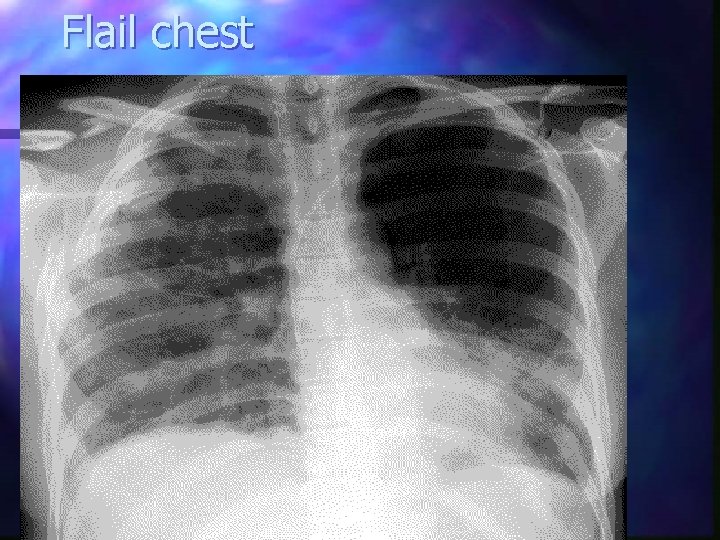

Flail chest Multiple rib fractures produce a mobile fragment which moves paradoxically with respiration n 2 or more ribs in 2 or more places n Significant force required n Palpate carefully and laterally n Rx: ABC s and analgesia n +/- splint the flail segment n

Flail chest

Flail Chest - detail